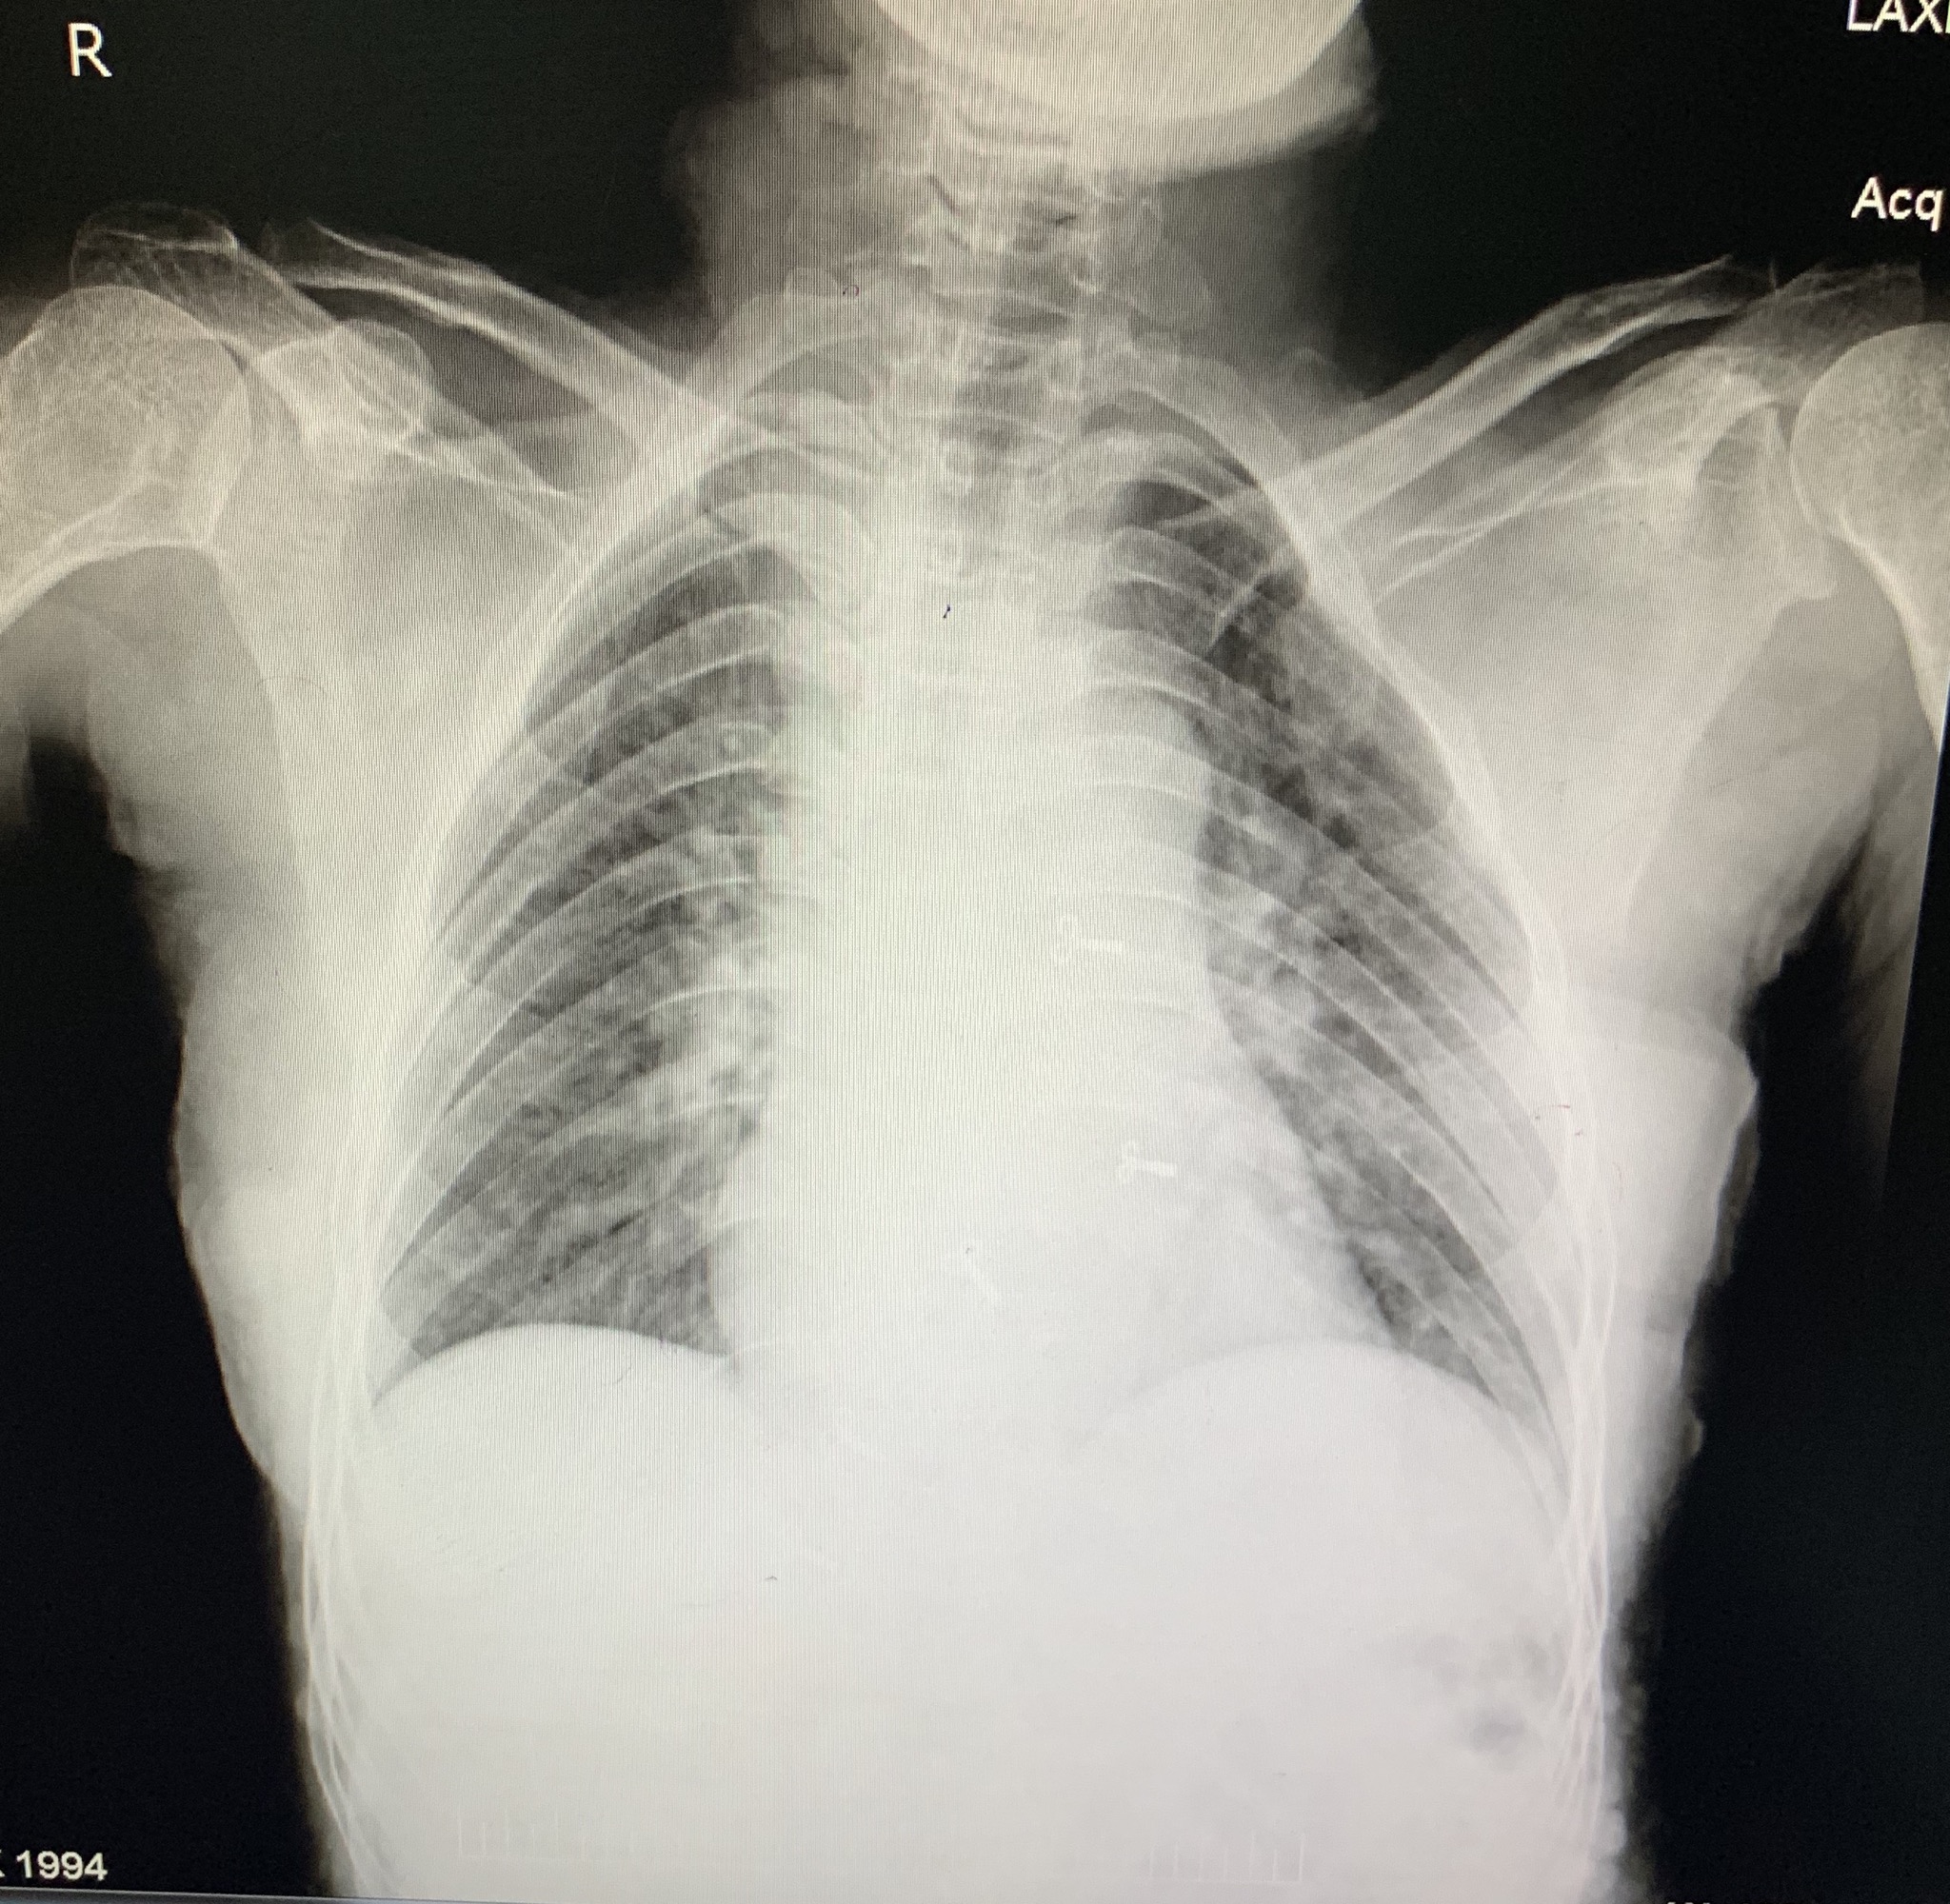

RS: BAE present, crepts + in Right IMA and right IAA